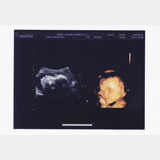

妊娠5ヶ月の超音波写真

初めて4Dで顔が見えた写真です。可愛くて仕方なくて、携帯でもさらに撮って毎日眺めていました。前日の夜に「お顔見せてね」と話しかけていたらちゃんと見せてくれました。

カメラ目線!!!

17週0日。先生が、こっちを向いて笑ってるっぽく映った画像を選んでくれました♪